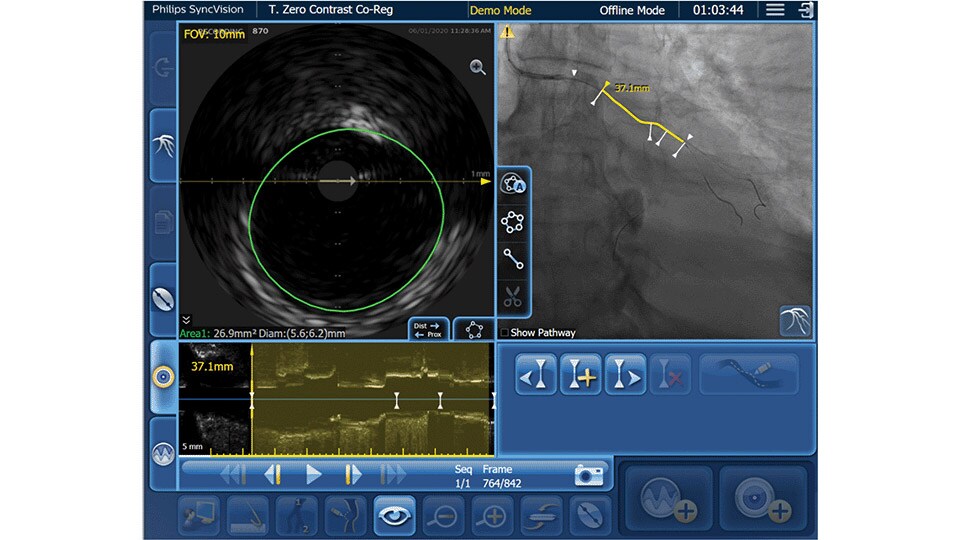

IVUS co-registration

Software helps you understand precisely where the disease begins and ends and guides your pre-and post-strategy decisions for improved outcomes.